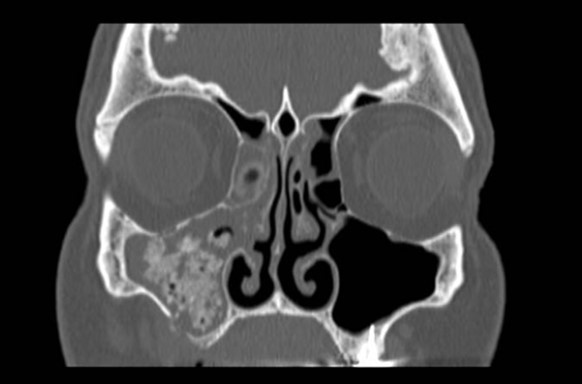

Figure 3 is a good example of implant preservation. This patient presented with psudomonas infection of the right maxillary sinus endangering the viability of the dental implant. The infection was drained by FESS and a few months later the patient had a repeat scan which showed complete resolution of the infection, ventilation of the maxillary sinus and the implant intact and secure.

Previously the assumption was that once the area around the implant is infected, the implant should be removed. However our current thinking is that as long as the implant is secure and integrated with no pain and is not loose, we should try our best to treat the infection and attempt to preserve the implant. This is particularly important with zygoma implants. To my knowledge they are very difficult to remove and therefore treating the sinuses before insertion of the implant is important, however should the area become infected but the implant is stable, we should try and preserve it.